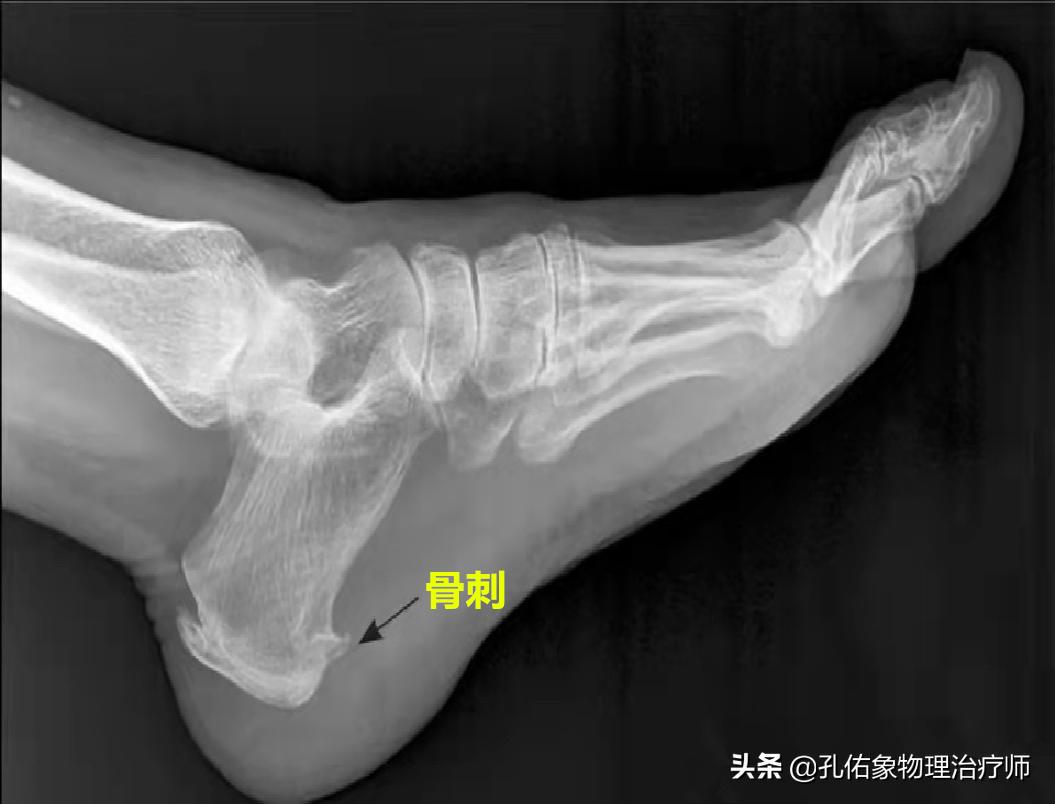

其实对于跟痛症而言,它的致病因素很多, 骨刺仅是影像学表现而已,并非是导致疼痛的根本原因。

您需要明白,骨刺与您的疼痛症状没有相关性,哪怕是拍了脚踝的X线片,上面长有骨刺,都不要误认为疼痛就是骨刺引起的; 因为骨刺的形成是足底跖筋膜与跟骨连接部位反复地出现撕裂瘢痕,最终钙化所致;其根源还是足底的跖筋膜。